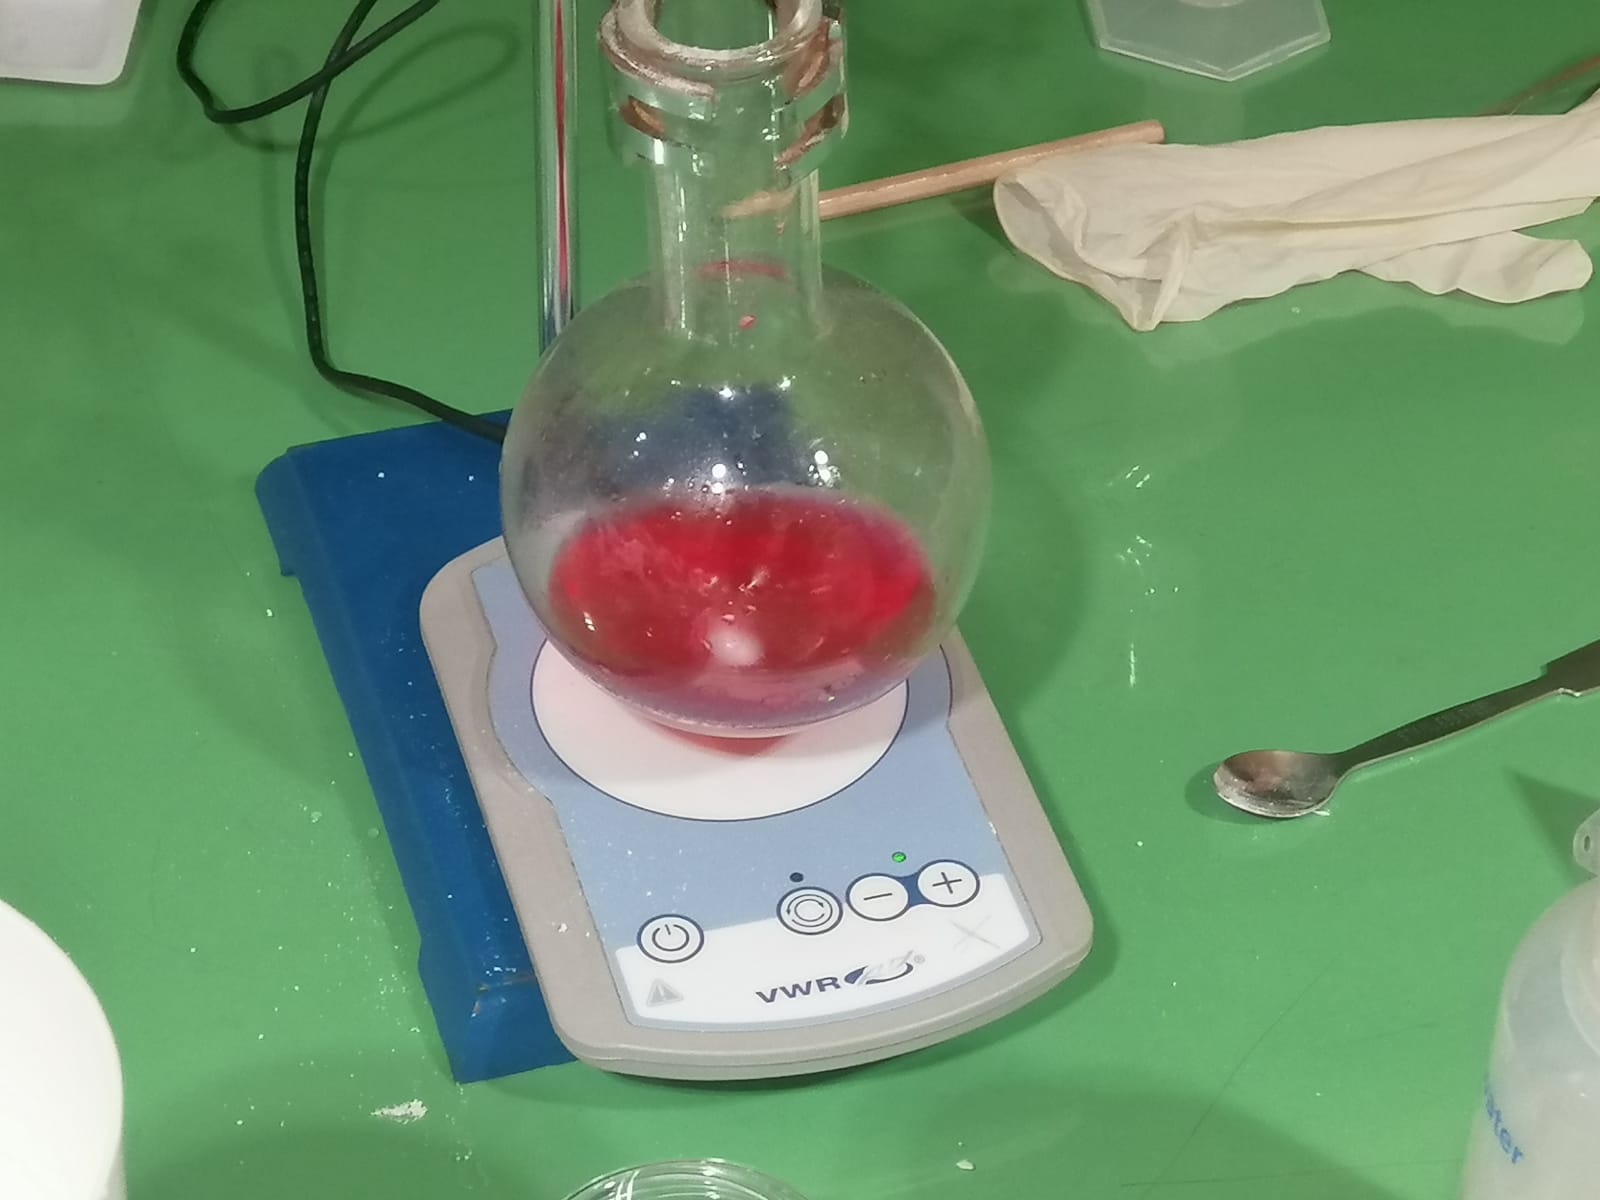

Aquesta setmana els alumnes de Química de 1r de Batxillerat han realitzat el Taller ‘Com es fan els medicaments’ al Parc Científic de Barcelona. El taller s’enmarca dins d’un projecte d’investigació per a nous fàrmacs que ajudin a tractar el Pàrkinson.

Paral•lelament, els alumnes de les optatives de Biologia i FiQ de 4t d’ESO han realitzat el mateix taller al CosmoCaixa aprofitant la col•laboració! Hem aprofitat la visita per a repassar els orígens de la vida a la Terra fent un recorregut per l’exposició permanent del museu.